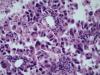

Опухоль легкого |

Карциноид...

Аденокарцинома со стелющимся типом роста (lepidic)

Тоже склоняюсь к бронхиолоальвеолярному раку.

Уважаемый Медик, добрый вечер! Поясните, пожалуйста, в чем существенная разница между БАР и предложенным мной вариантом? В своей работе я использую классификацию 2015 года, в которой БАР нет, это устаревший термин. Верно, с 2015г..БАР нет. В данном случае Аденкарцинома, lepidic тип👏 |